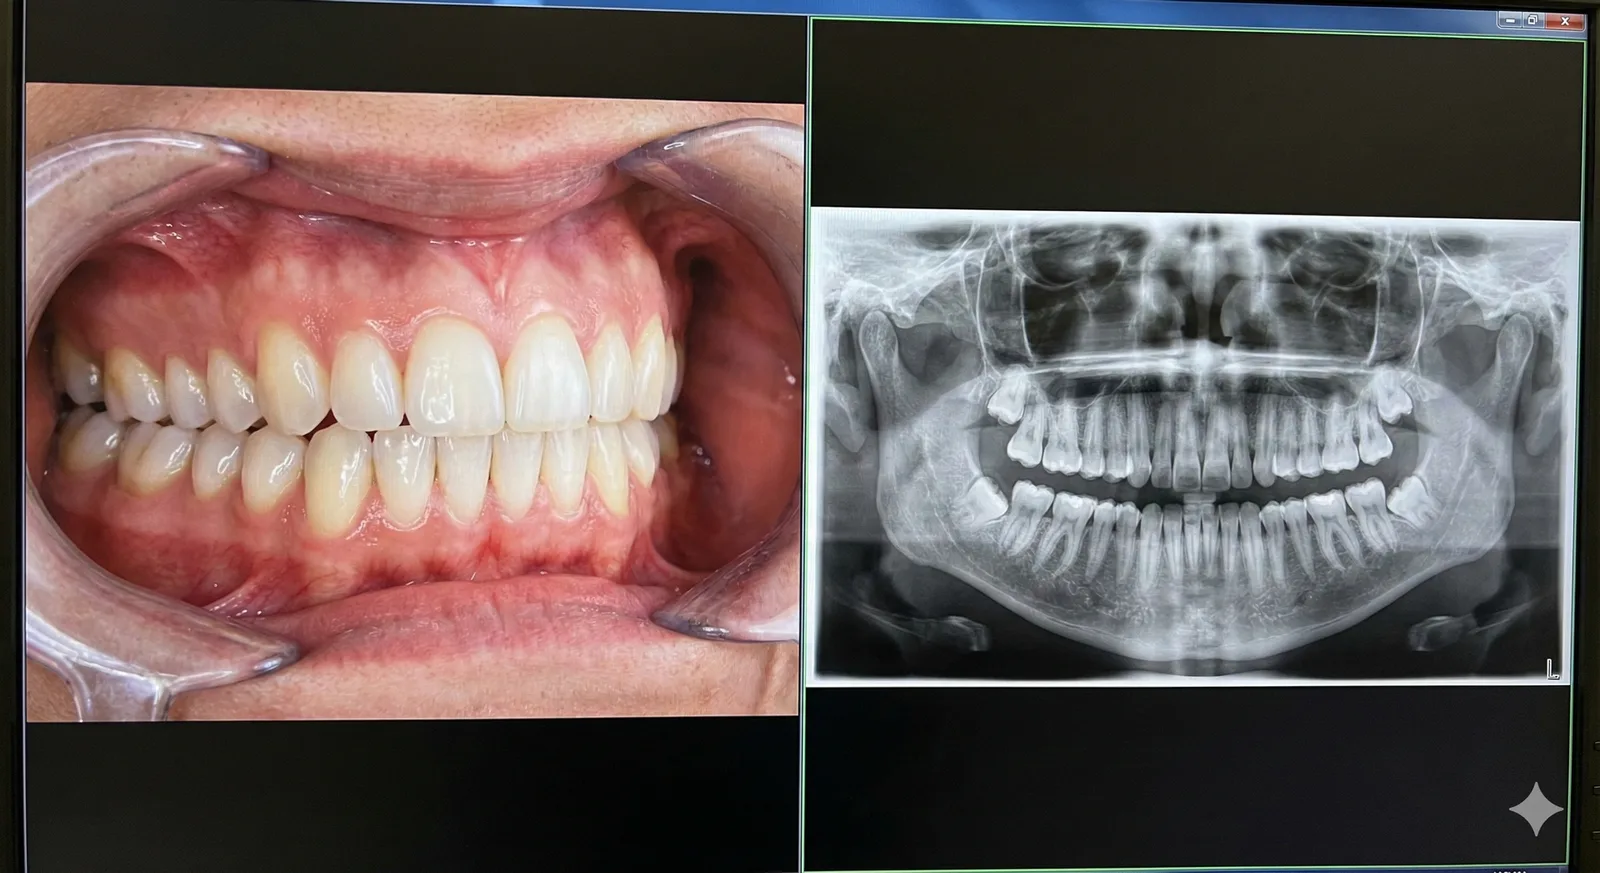

유치 상태, 영구치와의 교환 상태, 교합 변화 등을 성장 단계에 맞춰 평가하고 필요한 관리 방법을 안내합니다.